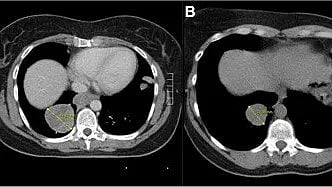

Two identical MRI scans displaying the same area for comparison and analysis.

Unlocking the future of ampullary adenocarcinoma cancer care: Exploring hidden prognostic factors to improve cancer survival and personalize treatment.Verschoor AJ, Gelderblom H, CC0/ Wikimedia Commons